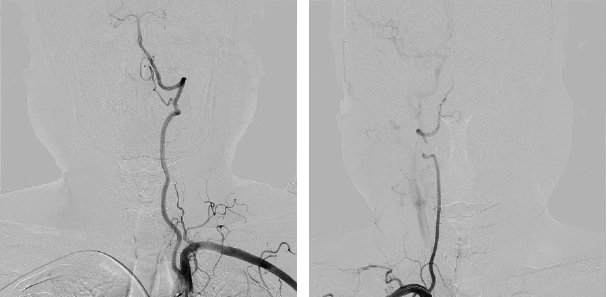

主動脈弓

左側頸動脈 / 右側頸動脈

左側椎動脈 / 右側椎動脈